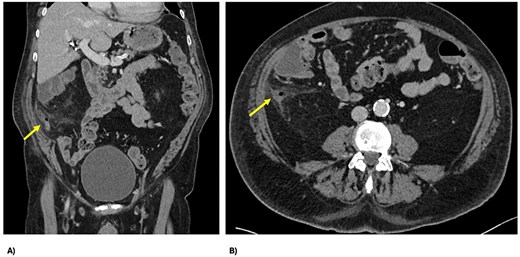

Two days post-embolization, the patient developed right-sided abdominal pain, localized abdominal tenderness and elevated inflammatory markers (white cell count 17 × 109/L, C-reactive protein 42 mg/L). Repeat computed tomography (CT) abdomen/pelvis showed perforated appendicitis with appendiceal mural thickening and extraluminal gas, not present on his initial imaging (Fig. 3). Treated non-operatively with intravenous antibiotics, his signs and symptoms resolved within 24 hours. He continued his recovery and was subsequently discharged on Day 11 for consideration of interval appendicectomy.

CT demonstrating perforated appendicitis post-embolization with a fluid collection and stranding, with the line of demarcation demonstrating hypoperfusion, suggestive of ischemia; (A) axial view and (B) coronal view.